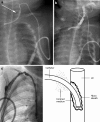

Central venous access is increasingly becoming the domain of the radiologist, both in terms of the insertion of central venous catheters (CVCs) and in the subsequent management of these lines. This article seeks to provide an overview of the CVC types available for paediatric patients and a more detailed explanation of the spectrum of complications that may lead to catheter malfunction. A standard catheter contrast study or 'linogram' technique is described. The normal appearances of such a study and a detailed pictorial review of abnormal catheter studies are provided, together with a brief overview of how information from catheter investigations can guide the management of catheter complications.